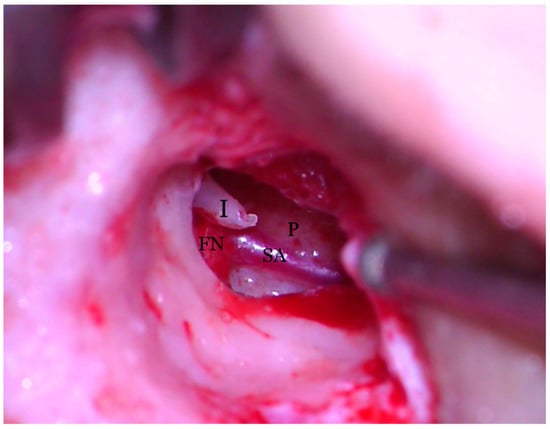

Hearing loss in patient’s right ear (with PSA) was addressed by performing an ossiculoplasty with a total ossicular replacement prosthesis (TORP). After a thorough preoperative planning based on prior surgical middle ear exploration and CT imaging, a transcanalar approach to the middle ear was used. A standard tympanomeatal flap was raised and the PSA was inspected. Large dimensions, complete coverage of the oval window site and crossing over the round window niche were again noted (Figure 7). The PSA went superiorly across the promontory and entered the facial nerve canal at the level where the normal oval window niche would have been located. Successful cochleostomy was carried out with a diamond burr posteriorly to the PSA and inferiorly to the facial nerve canal. Perichondrium was used to seal the cochlea opening and also served as a support for a total replacement ossicular prosthesis (Figure 8). The TORP was seated in place and covered with a mixed graft of cartilage and perichondrium with the tympanic membrane on top of it (Figure 9 and Figure 10).

Figure 7.

Transcanalar microscopic aspect of right middle ear: the Stapedial Artery (SA) can be seen runnning across the promontory (P) and joining with the facial nerve (FN) right under the incus (I) long process.